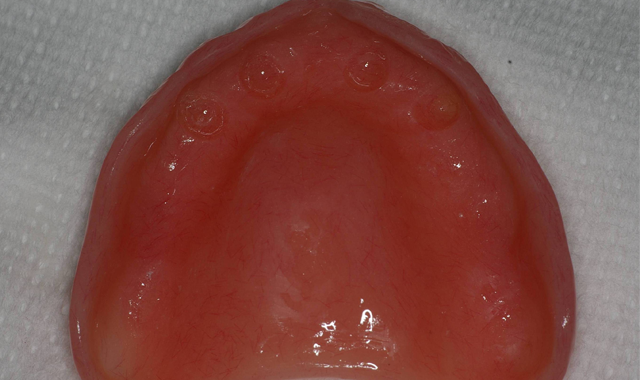

Once the impressions, relations, shade and opposing model were forwarded to the dental lab, the metal-reinforced, palate-free overdenture was initiated.

Approximately three to four months later, the previously made metal-reinforced overdenture with relieved areas for the housings was tried in to confirm comfort and fit. Any interference that was detected between the denture base, attachments and housings was checked and eliminated (Fig. 9).

Fig. 9 Fig. 10

When relining dentures or picking up overdenture attachments directly within the mouth, the patient may experience heat generation that’s uncomfortable - in addition to a bad taste - when using methyl methacrylate. Since Tokuyama® Rebase II Hard Denture Chairside Reline (Fig. 10) is methyl methacrylate free, it doesn’t have a strong odor or taste and features minimal heat generation, making it a much better experience for the patient. Given this and its high durability and mechanical properties, I used Rebase II as a pickup material in implant procedures.

Fig. 11 Fig. 12

The first step was to brush a thin coat of adhesive into the overdenture recesses to enhance retention between the denture base and the hard reline. Petroleum jelly was applied to the surrounding surfaces of the denture to prevent unwanted adherence of excess material. Once mixed, the Tokuyama Rebase II material (Fig. 11) was placed into a plastic dispensing syringe and injected up to two-thirds the height of each recess as well as onto the attachments. During seating, the prosthesis was gently held in place by hand.